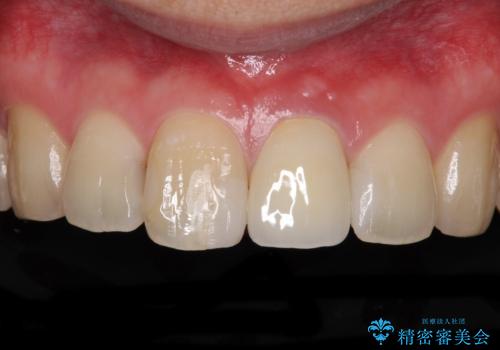

歯髄は既に壊死していたため、根管治療を行い、その後オールセラミッククラウンにて補綴することとしました。

変色による周囲に視線が気にならなくなり、明るいくらいとなりました。